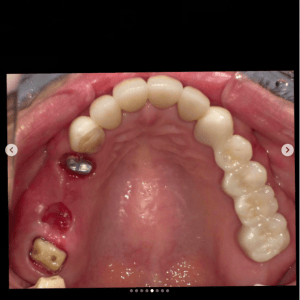

審美歯科症例集(ビフォーアフター)

より多くの症例をこちらのページでご紹介しておりますので、合わせてご覧ください

Case032

広島からの患者様です。

前歯を綺麗にしたい。インプラントをしたい。

という主訴で東京の歯医者をいろいろ調べて当院を選んでくださいました。

毎回、遠い中しっかり通ってくださり、選んで頂けた嬉しさと、その気持ちに応えたいという想いで診療させて頂きました。

前歯はご希望のお色でラミネートベニアでは出せない透明感のあるセラミックに上下左側7はインプラントをさせて頂きました。

左上は破折で温存不可。

骨も少なかったので、サイナスリフトも行い計五回の来院で被せ物を入れさせて頂きました。

左下は前回のクリニックでの埋入位置が深すぎて食べカスも毎回詰まる、セルフメンテナンスではら汚れも取れない。インプラント周囲炎にもなっていたので、一度前のインプラントを除去し、そこから新しくインプラントを埋入し、診療させて頂きました。

インプラント、歯並び、審美歯科にご興味のある方はいつでも相談にお越しください。

担当 理事長 佐藤 悠野